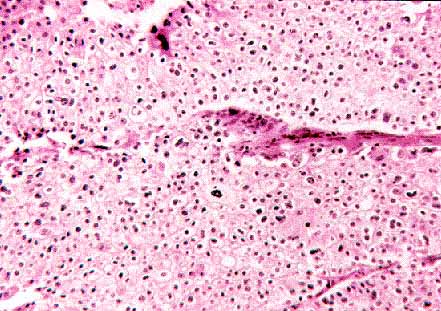

fig. 1

Figura 1.- Carcinoma de células cromófobas putativo que cumple los criterios adecuados en 4 de los 6 apartados establecidos. Se observan numerosas figuras de mitosis, algunas vacuolas “vacías” citoplásmicas y una anisocariosis relevante. (H&E, 200X)